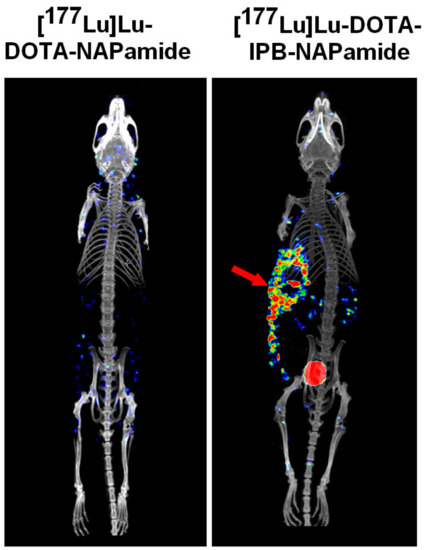

2.3.3. In Vivo and Ex Vivo Biodistribution Pattern of [177Lu]Lu-DOTA-NAPamide and [177Lu]Lu-DOTA-IPB-NAPamide

| Organ/Tissue | [177Lu]Lu-DOTA-NAPamide (%ID/g) | [177Lu]Lu-DOTA-IPB-NAPamide (%ID/g) |

|---|---|---|

| blood | 0.02 ± 0.02 | 3.71 ± 0.73 ** |

| liver | 0.24 ± 0.13 | 1.97 ± 0.13 ** |

| spleen | 0.07 ± 0.04 | 1.32 ± 0.20 ** |

| kidney | 1.85 ± 0.79 | 5.58 ± 1.59 |

| small intestine | 0.01 ± 0.01 | 0.60 ± 0.03 ** |

| large intestine | 0.02 ± 0.02 | 0.61 ± 0.11 ** |

| stomach | 0.02 ± 0.01 | 0.69 ± 0.11 ** |

| muscle | 0.00 ± 0.00 | 0.33 ± 0.07 ** |

| lung | 0.04 ± 0.03 | 2.50 ± 0.24 ** |

| heart | 0.01 ± 0.00 | 1.30 ± 0.12 ** |

| brain | 0.00 ± 0.00 | 0.08 ± 0.01 ** |

| fat | 0.01 ± 0.01 | 0.67 ± 0.34 ** |

| B16-F10 tumor | 0.16 ± 0.15 | 4.16 ± 1.86 ** |